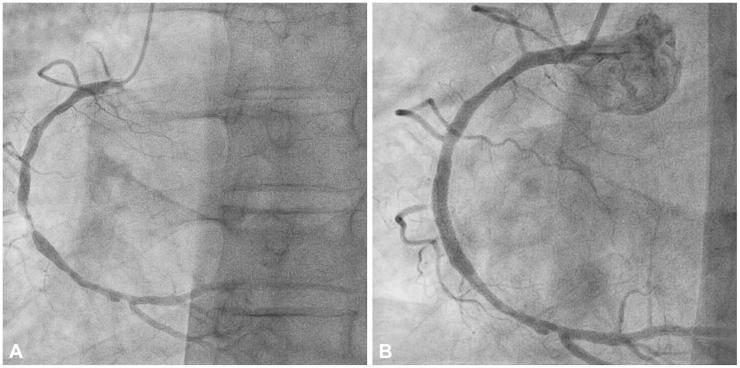

Non-cardiogenic pulmonary edema (NCPE) is a rare adverse reaction to iodinated radiocontrast media (RCM), in which all previous cases were immediate reactions. A 56-year-old male was given iopamidol, a non-ionic, low osmolar RCM, during coronary artery angiography. He developed pulmonary edema and fever a day after the procedure. Despite diuretic therapy, the patient's pulmonary edema worsened and his high fever persisted. The patient's pulmonary edema was eventually resolved with intravenous steroid treatment. We interpreted the patient's condition as NCPE manifesting as a delayed reaction to RCM. To our knowledge, our case is the first to show NCPE as a delayed hypersensitivity reaction.

非心源性肺水肿(NCPE)是碘造影剂(RCM)罕见的不良反应,此前所有病例均为即刻反应。一名 56 岁男性在冠状动脉造影期间使用了一种非离子型、低渗的 RCM 碘帕醇。在操作后一天,他出现肺水肿和发热。尽管给予利尿剂治疗,但患者的肺水肿仍恶化,高热持续。患者的肺水肿最终通过静脉注射类固醇治疗得到缓解。我们将患者的病情解释为 RCM 迟发性过敏反应引起的 NCPE。据我们所知,我们的病例是首例显示 NCPE 为迟发性过敏反应的病例。